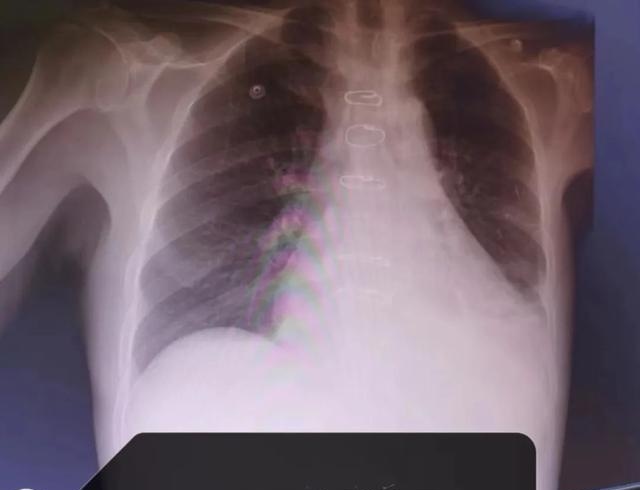

为求进一步诊治,李先生来到长沙泰和医院心胸外科就诊。完善相关检查诊断为:冠心病,慢性心力衰竭,2型糖尿病视网膜病变,2型糖尿病神经病变,2型糖尿病肾病,化验结果报危急值,心脏彩超提示心脏功能射血分数37%,心功能极差,暂时没有手术指征。因此,接诊的心胸外科专家建议先转入我院心内科改善心功能后再行手术治疗。

心血管内科对李先生予以对症治疗心衰后,复查心脏彩超心脏射血分数为47%,已有手术指征后转入心胸外科。长沙泰和医院心胸外科白振祥主任带领科室团队组织连线万峰专家技术团队,并联合麻醉科、手术室、ICU等组成的多学科团队进行MDT术前讨论,在详细评估患者的手术方案及术中、术后可能出现的各种情况后,最终决定在“心脏不停跳”的基础上,进行冠状动脉旁路移植手术。

术后,李先生胸闷气促等不适症状明显好转,复查心脏彩超提示射血分数为52%。经过ICU和心胸外科团队精心治疗后,恢复良好,现已顺利康复出院。